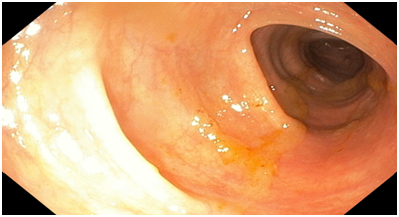

Colonoscopy. The colonoscope was passed all the way down to the ascending colon (distal part). The ascending colon contained circumferential fungating necrotic mass lesion extending all the way down to the caecum. The mass was friable, bled easily both spontaneously and with contact. Multiple biopsy samples were taken from the mass. There was some degree of luminal narrowing as well. The rest of the examined colon all appeared normal. No diverticulum or polyp seen. No observable synchronous tumour seen. Endoscopic Diagnosis was Right-sided colonic adenocarcinoma.

Figure 2 An Endoscopic image of the Ascending colon showing the tumour extending all the way to the cecum.